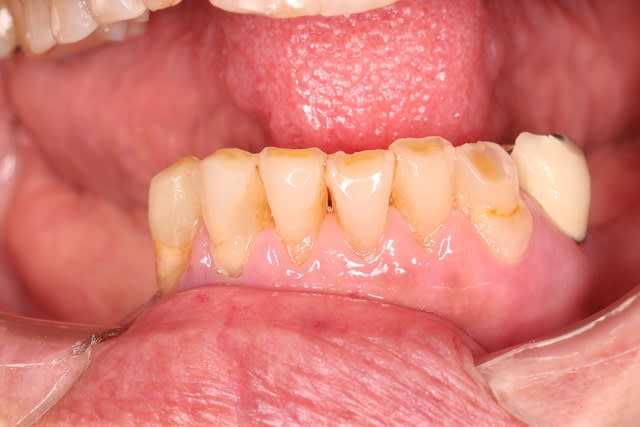

Le bas, on garde ou on vire ? 34 mobile, le reste ça bouge pas.

sinon pour le bas je vire pas si le patient en fait pas la demande ou ne signe pas pour au moins des locator.

Oui , aller,,on garde le bas qui nous servira de repère pour faire le haut

Je garderai tout ce qui ne bouge pas en bas. Virer des dents immobiles et asymptomatiques c'est sévère ! ;) Un bon bloc d'ancrage pour le stellite.

Par contre, sans implants, durée de vie estimée des 33 / 43 avec un crochet qui tire dessus ?

de toute facon , le stellite ne servira pas de calage , il sera tres tres vite en sous occ . avec un joli crochet qui va flotter , donc autant faire un crochet bien souple .

je pense que c est plus l'occlusion qui finira les canines , sauf si CCAM en bas aussi .